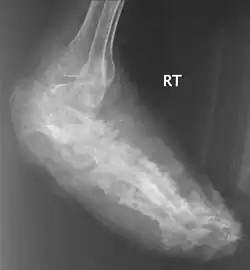

X rays and ultrasonography may be carried out to assess the extent of the disease. X rays findings are extremely variable. The disease is most often observed at an advanced stage that exhibits extensive destruction of all bones of the foot. Rarely, a single lesion may be seen in the tibia where the picture is identical with chronic osteomyelitis. Cytology of fine needle aspirate or pus from the lesion, and tissue biopsy may be undertaken sometimes.[11] Some publications have claimed a "dot in a circle sign" as a characteristic MRI feature for this condition (this feature has also been described on ultrasound).[14]

Madura Foot X-Ray